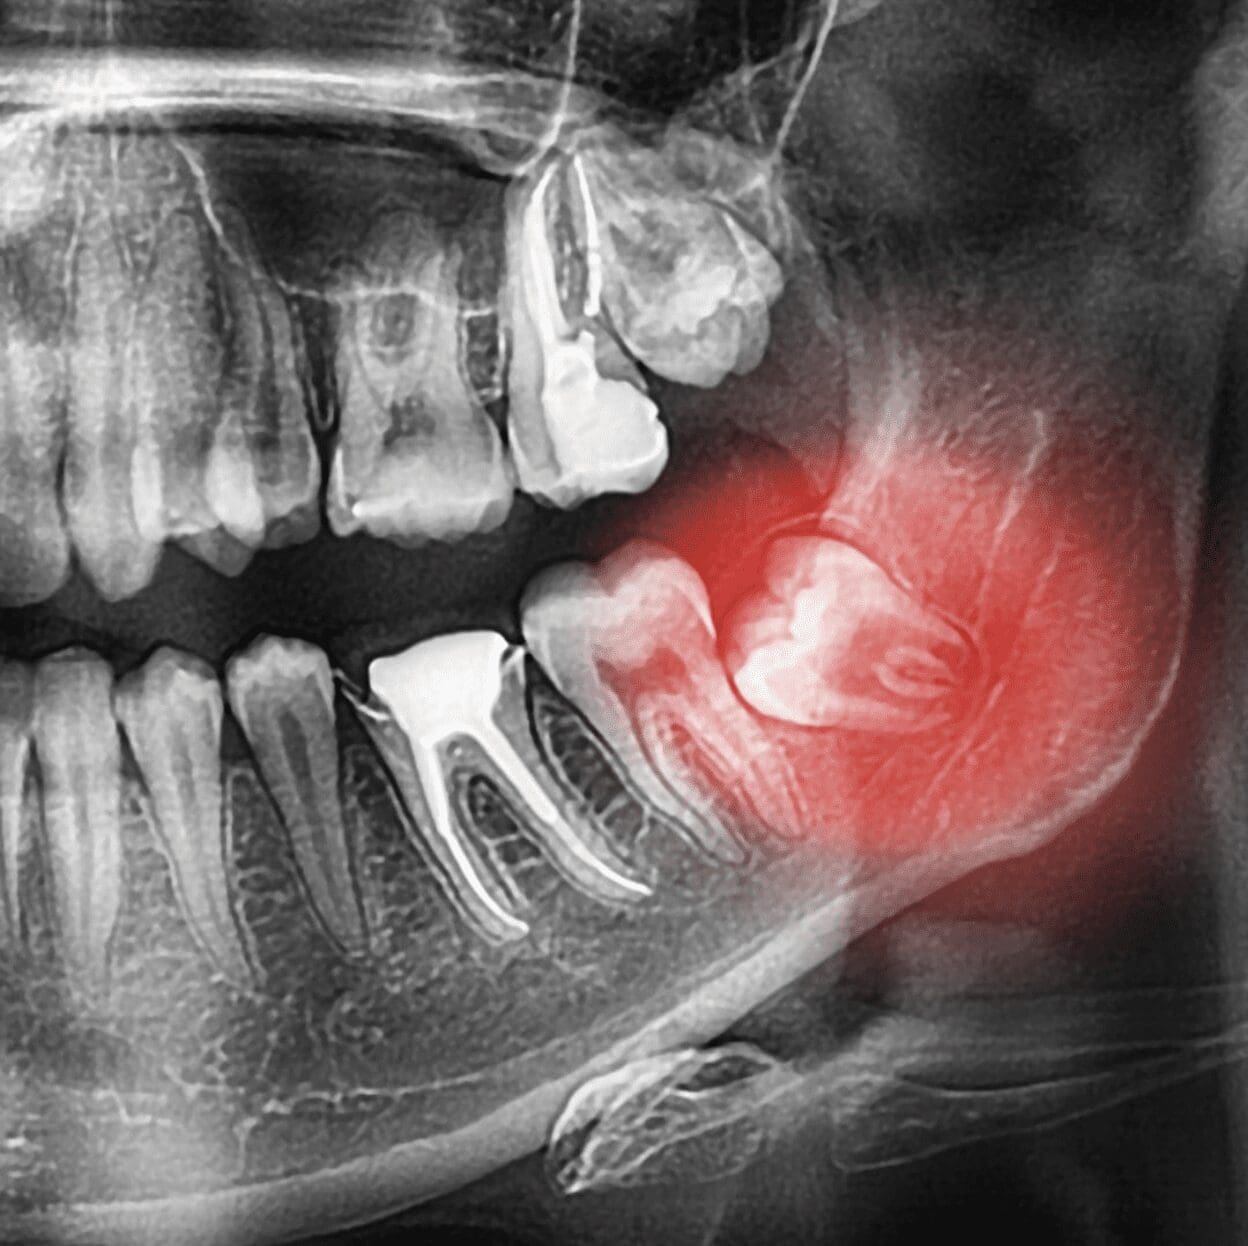

Overcrowded and Impacted Teeth

Teeth that are overcrowded, impacted, or rotated may need extracting. This is the case when they don’t have enough room to come into contact with each other properly. Ingesting an object that is too big may also cause your teeth to rotate, leading to extraction.

Your dentist will use dental pliers to grab the tooth and twist it to pull out these teeth. The process may be quick, but it can also be uncomfortable because you’ll feel the tooth pulled out.